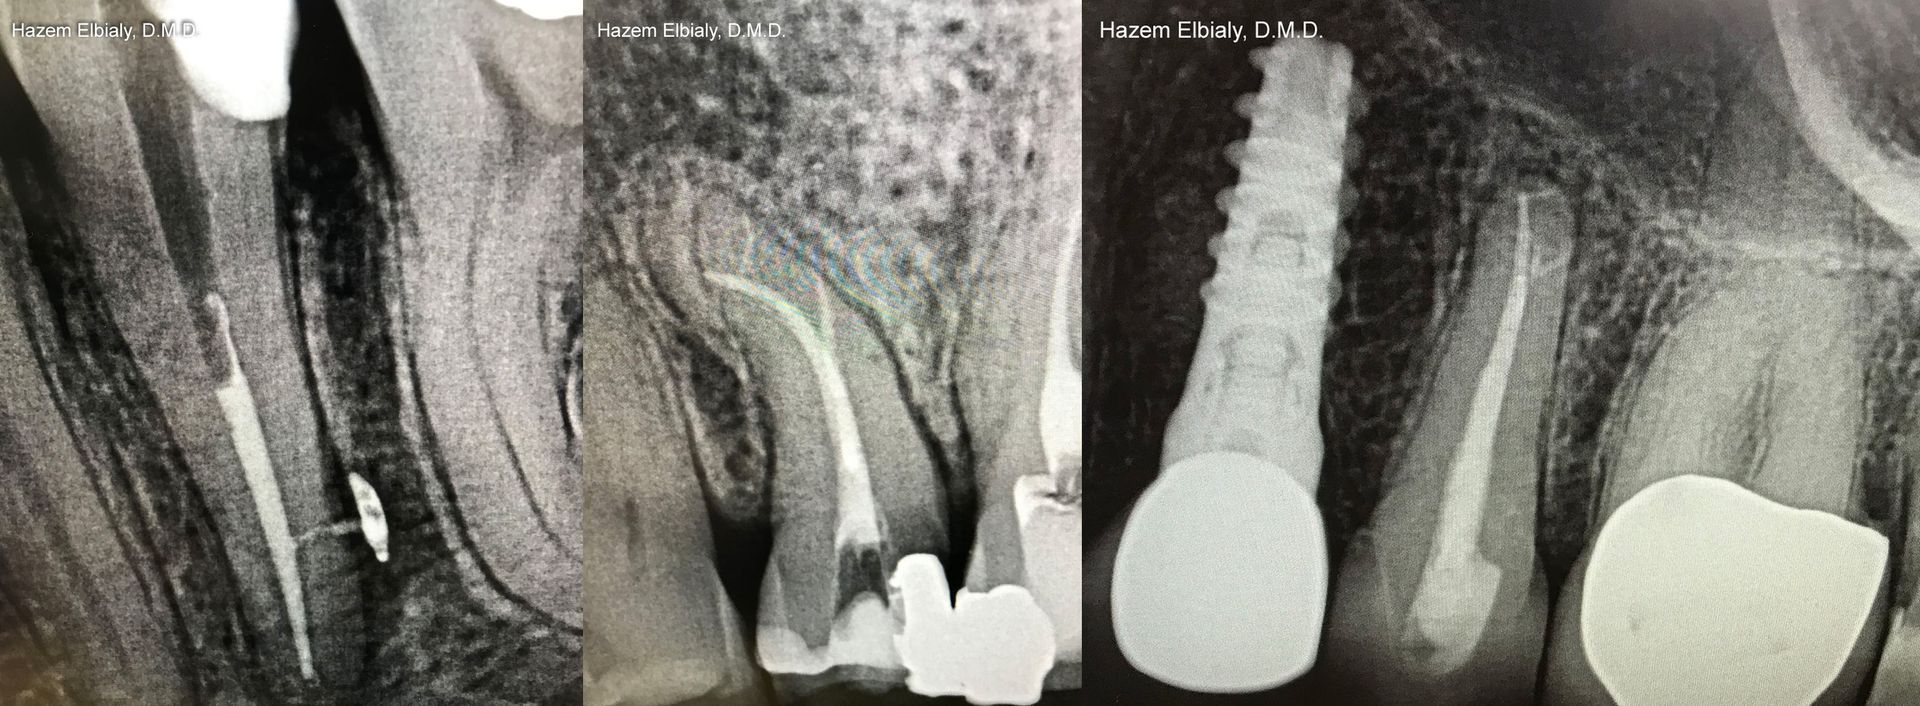

Our root canals are quick and painless. Dr. Elbialy ensures you are adequately anesthetized and comfortable before beginning the procedure. He uses an electronic apex locator and NiTi instruments for speed, pinpoint precision, and accuracy.

- Type of Crown: Because the internal structure of a tooth is removed during a root canal, a crown is necessary to ensure it remains stable. Crowns can be made of various sizes and materials.